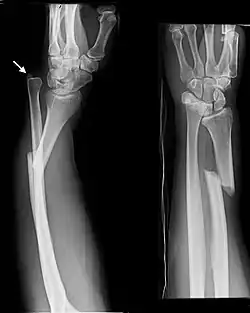

- Monteggia fracture - a fracture of the near to elbow end of the ulna with the dislocation of the head of the radius at the elbow joint.[2]

Monteggia Fracture (fracture of proximal ulna)

- Distal ulna fractures typically occur along with distal radius fractures.[3]

- Galeazzi fracture - not a fracture of the ulna but a displaced fracture of the radius accompanied by a dislocation of the ulna at the wrist, where the radius and ulna come together.[2]

Galeazzi facture (displaced fracture of the radius)